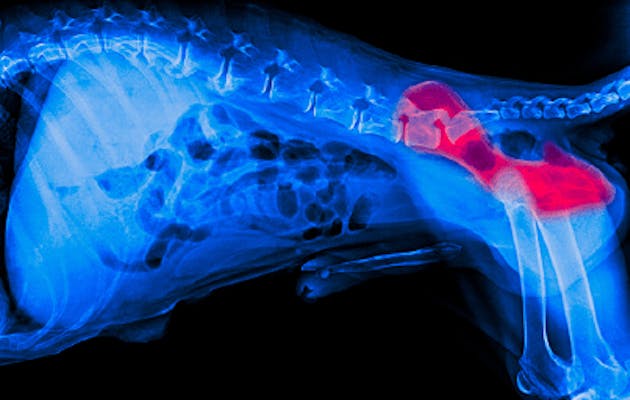

Akkurat som hos mennesker, kan slitasje på brusken føre til stivhet, smerter og redusert bevegelse hos hunder. Når den naturlige støtdempingen i leddene brytes ned, blir selv enkle bevegelser vonde – og livsgleden reduseres.

Studier viser at kollagen type II kan styrke brusk, redusere ubehag og forbedre bevegelighet hos hunder – på en naturlig og skånsom måte.

Styrker ledd og brusk – Kollagen og gurkemeie støtter bevegelighet og komfort

Lindrer stivhet og ubehag – Ideelt for eldre hunder eller etter skade